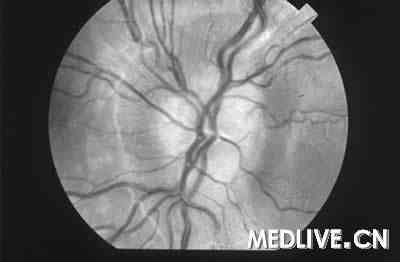

T 36.0℃,P 104次/min,R 20次/min,BP 245/130 mmHg。一般状况:发育良好,轻度嗜睡。胸部:两肺底可闻及啰音。心血管:心动过速,S1正常,S2亢进,可闻及S3,在胸骨右缘可闻及Ⅱ/Ⅵ收缩期杂音,不向颈部传导。颈静脉压轻度升高,桡动脉和足背动脉搏动存在。四肢:双下肢远端水肿。神经系统:失语,瞳孔反应迟缓。右侧偏瘫,偏身感觉障碍。颅神经正常。右侧深部腱反射亢进,左侧正常。眼底镜检查:有动静脉交叉征,可见铜丝征和视乳头水肿(见图)。

图1 眼底镜检查:有动静脉交叉征、视乳头水肿